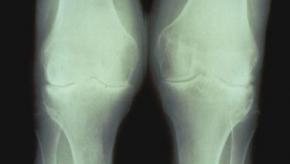

Read ArticleBad Knees Through the Ages

The average American today is twice as likely to be diagnosed with knee osteoarthritis as in the years before World War II, Harvard scientists say. And the reasons are less clear than you might think.Based on a study of more than 2,000 skeletons from cadaveric and archaeological collections across the United States, a Harvard report is the first to definitively show that knee osteoarthritis prevalence has dramatically increased in recent decades.